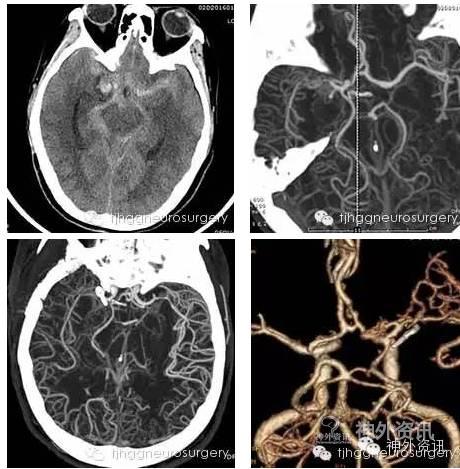

罗婆婆今年56岁,在外打工的女儿女婿打电话回来说这个春节在咱家过,婆婆心里乐开了花,早早在家扫尘土,弯腰扫出床下积灰时突感剧烈头痛、难以坐立,老伴立即呼叫120急救车急送我院急诊科,头部CT发现颅内蛛网膜下腔出血,高度怀疑颅内动脉瘤。颅内动脉瘤不易于颅内埋有一颗炸弹,何时引爆,难以预计,一旦破裂重者致命。对于罗婆婆颅内有无此类炸弹、具体方位如何亟需明确,若有炸弹则这一炸弹必已火星四射蠢蠢欲动,不及时排拆,患者随时有生命危险。

虽然临近佳节,雷霆教授、张华楸副教授、李小玲护士长领衔的医护团队立即联系放射科、麻醉科、手术室等相关科室医务人员组建多学科合作组,短时间内完成了血管造影检查,发现了婆婆头痛的元凶和方位。随后在麻醉科梅伟教授、手术室陈红护士长领衔的麻醉手术团队的协作下,顺利排爆,显微夹闭了罗婆婆颅内的动脉瘤。术后经过我科护士们的精心照料,罗婆婆恢复良好。